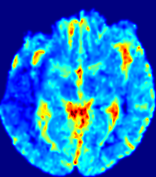

Figure 4: PIANO feature maps for another patient in the ISLES 2017 training set, where the lesion is located in the right hemisphere. Top row: segmented stroke lesion region (white) on different slices. The corresponding slices for the PIANO feature maps are shown in the following rows.

For a better insight into an estimated velocity field 𝐕𝐕{\bf{V}} and diffusion field 𝐃𝐃{\bf{D}}, we compute the following maps: (1) 𝐕rgbsubscript𝐕𝑟𝑔𝑏{\bf{V}}_{rgb}: Color-coded orientation map of 𝐕=(Vx,Vy,Vz)T𝐕superscriptsuperscript𝑉𝑥superscript𝑉𝑦superscript𝑉𝑧𝑇{\bf{V}}=(V^{x},V^{y},V^{z})^{T}, obtained by normalizing 𝐕𝐕{\bf{V}} to unit length and mapping its 3 components to red, green, blue respectively; (2) 𝐕2subscriptnorm𝐕2\|{\bf{V}}\|_{2}: 222 norm of 𝐕𝐕{\bf{V}}; (3) D𝐷D: scalar field in Eq. 5.

Fig. 3 and Fig. 4 show the PIANO feature maps estimated from two ISLES 2017 patients: all are highly consistent with the lesion in both cases. Details of the blood flow trajectories are revealed in 𝐕rgbsubscript𝐕𝑟𝑔𝑏{\bf{V}}_{rgb} by the ridged patterns and the sharp changes of colors in the unaffected (right) hemisphere, while the flat patterns appearing within the lesion provide little directional information about the velocity and indicate low velocity magnitudes. Velocity magnitudes are more directly visualized via 𝐕2subscriptnorm𝐕2\|{\bf{V}}\|_{2}, from which one can easily locate the lesion where 𝐕2subscriptnorm𝐕2\|{\bf{V}}\|_{2} is low. D𝐷D also indicates lower diffusion values in the lesion, though with less contrast potentially due to the fact that it captures the accumulated effect of CA diffusion at the voxel-level.